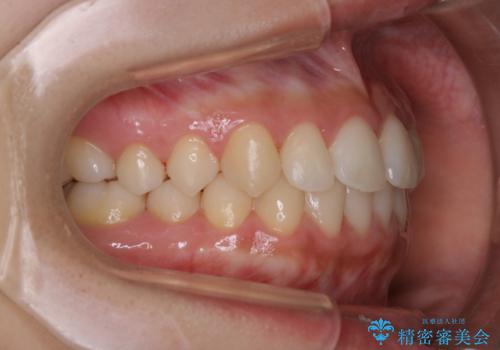

- 矯正治療が終了したため、クリーニングでもきれいにしたいとのことでした。PMTC60分コースを行いました。

矯正治療が終わり、せっかくきれいになった歯並びも、虫歯・歯周病などになってしまっては元も子もありません。

ご自身での歯ブラシ・セルフケアを行うと同時に、定期的なクリーニング(PMTC)を行うことで、いつまでも健康な歯を保つことができます。